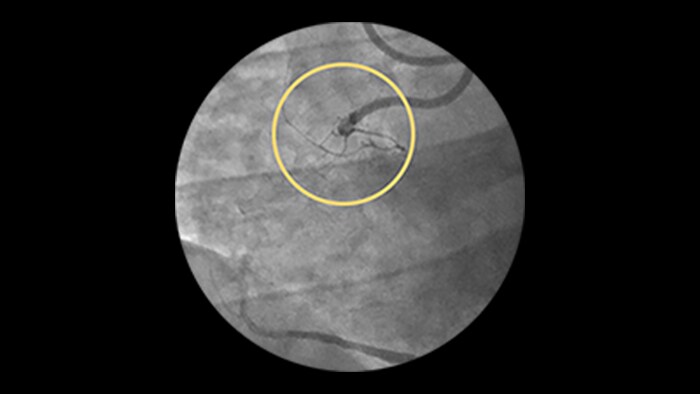

Device detection

Enhanced stent visualization quickly verifies positioning before and after deploying balloons and stents.

Dynamic Coronary Roadmap

This Philips-exclusive technology provides a real-time view of the coronary arteries and removes the need for additional contrast injections.

StentBoost

This simple, quick and cost-effective tool enhances stent visualization in the coronary arteries.